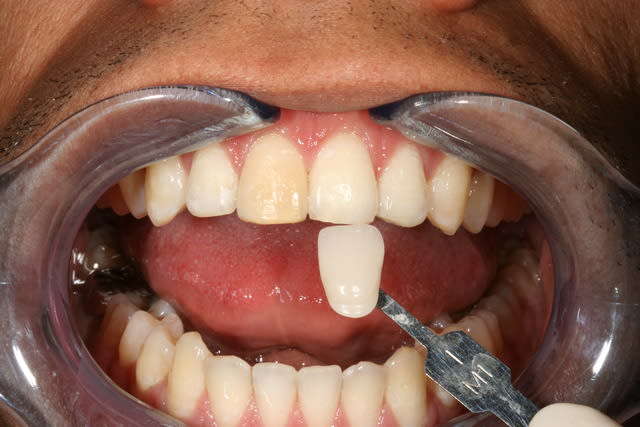

PS/ Je prolonge le ttt jusqu'à la semaine prochaine en espérant gagner encore un poil sur l'opacité .

Le protocole est le même que pour une dent dépulpée ; isolation en regard présumé du canal , un peu plus parce que j'ai cherché un moment en plusieurs séances . Perborate , et voilà .

3 séances à 7 jours d'intervalles .

Si on décide d'être le moins invasif , j'ai jugé raisonnable de tenter quand même malgré l'impossibilité de repérage de l'entrée du canal . Faire une facette c'est passer un cap , et je n'ai de prothésiste capable de reproduire les stries visibles sur la photo de départ de tout façon donc je n'ai compté que sur moi même .